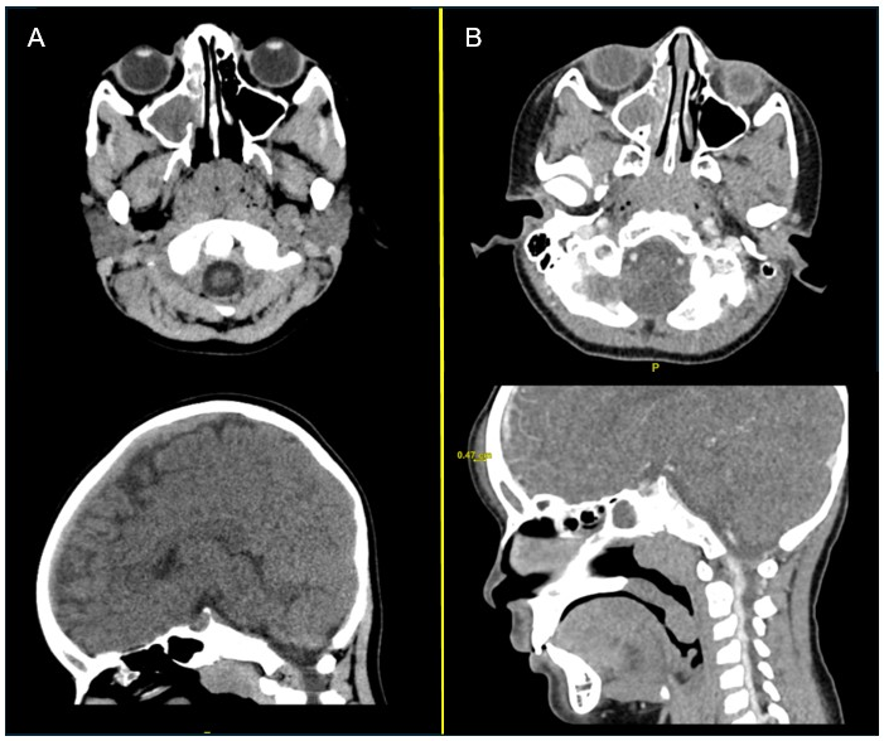

The patient subsequently presented to the emergency department for headache 3 days later. His vitals were within normal limits. A non-contrast head CT was unremarkable except for asymmetric opacification of the right maxillary sinus (Figure 1A). The patient was discharged with a prescription for ondansetron and told to follow-up with the outpatient pediatrician in 1-2 days. However, the patient subsequently re-presented to the emergency department on the following day due to continued headache and new frontal scalp swelling. He was afebrile and vital signs were stable. On physical examination, the patient had tenderness to palpation of the bilateral frontal and maxillary sinuses, but no meningismus. Otoscopic examination was unremarkable. However, his laboratory tests indicated mild leukocytosis (12.36k/mcL) and mild lymphocytosis (5.3k/mcL), with SARS-COVID-19 and influenza negative. CT maxillofacial with contrast was remarkable for interval development of frontal subcutaneous scalp thickening or edema with associated frontal sinus disease (Figure 1B). There was opacification of the anterior right ethmoid air cells, right frontal ethmoidal recess, and the aerated right frontal sinus. No osteolytic or erosive changes or drainable fluid collections were noted. The patient was given 2 g of ampicillin-sulbactam IV while in the emergency department prior to transfer to a tertiary hospital.

Fig. 1A-B (A) CT head non-contrast axial and coronal views during first visit to emergency department are shown. An opacification of the right maxillary sinus can be seen. (B) CT maxillofacial with contrast axial and coronal views during the second visit to the emergency department, taken 42 hours after image A is shown. Continued opacification of the right maxillary sinus and frontal sinus and interval development of frontal subcutaneous scalp thickening or edema, approximately 0.5 cm thick can be seen.